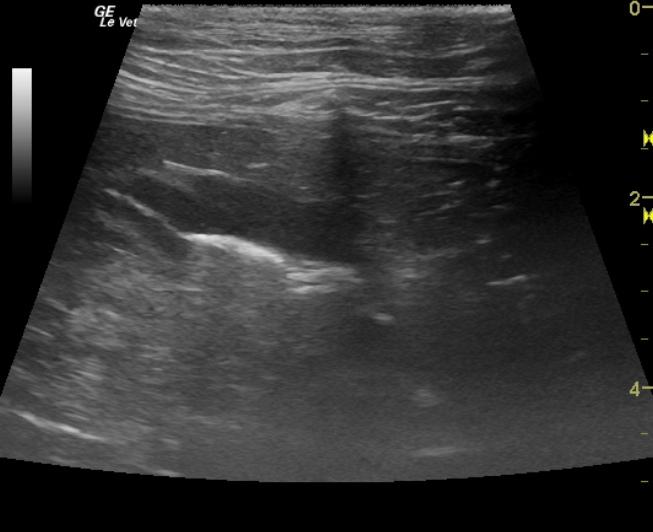

The gastrointestinal tract was normal in the region of the stomach and pylorus. The distal small intestine and jejunum presented minor areas of loss of detail with reactive omentum and large dramatically hypoechoic mesenteric root lymph nodes with significant loss of detail. Reactive omentum was also present suggestive of transmural pathology within the intestine and lymph nodes. The largest lymph node measured approximately 8cm in length.